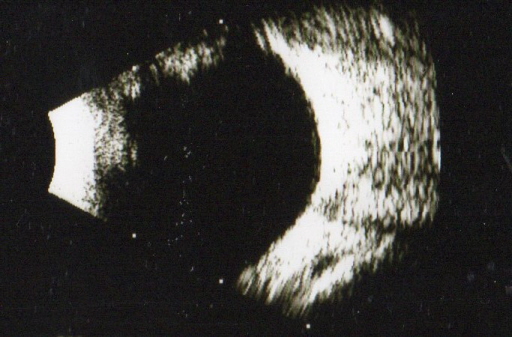

因飛蚊症憂鬱到想輕生 台日聯手救援澳洲工程師 |2021.08.16 語音朗讀 895觀看次 字級 大 中 小 圖/unsplash 【本報綜合訊】住澳洲東海岸的28歲工程師阿納夫Ahnaf,5年來飽受飛蚊症困擾到想輕生,後來在網路上看到日本防衛醫科大學與台灣合作研發的口服綜合水果蛋白酶能增強人體吸收眼睛玻璃體混濁機能,抱一絲希望寫信求助,信件轉至台灣參與研究的輔英科大附醫眼科醫師洪啟庭手中,洪展開跨海協助,解決這名工程師的眼疾困擾,重新恢復正常生活。日本防衛醫科大學轉給眼科醫師洪啟庭的救助信,來信者是為飛蚊症所苦的澳洲籍年輕工程師Ahnaf。圖/洪啟庭醫師提供洪啟庭是於今年5月間接獲日本防衛醫科大學轉來的電子郵件,來信者是澳洲籍年輕工程師Ahnaf,自述雙眼近視250度,5年前出現飛蚊症,常見長條帶些透明的浮游物在眼前漂浮,嚴重影響工作及生活。洪啟庭表示,Ahnaf寫信的前一個月因飛蚊頻率大增,憂鬱到精神科就醫甚至想輕生,後來在網路上看到台日合作研發的口服綜合水果蛋白酶,寫信向日本防衛醫科大學求助,日方把信交給參與研究的他,他隨即聯繫外交部亞太司與澳洲駐台辦事處人員透過管道將口服綜合水果蛋白酶交到Ahnaf手上,Ahnaf約2個月後生活恢復正常,情緒也好轉。澳洲求助者右眼的玻璃體混濁情況,後來獲得改善。圖/洪啟庭醫師提供洪表示,飛蚊症是因眼睛玻璃體隨年齡退化、眼部外傷、紫外線曝曬或PM2.5侵襲,造成眼睛玻璃體主要成分玻尿酸分解與眾多種類膠原纖維蛋白破壞,產生玻璃體液化與混濁及各種蛋白的雜亂排列,光線進入眼睛時,玻璃體混濁的部分會遮擋光線使影像成為陰影。由於目前尚無明確的治療方法,醫界通採觀察追蹤方式,據統計,約11%患者在1個月至5年後症狀會自行消失,64%視力降低,14%可能會視網膜剝離失明。2015年起,洪啟庭與仁科大學製藥研究所長謝博、日本防衛醫科大學眼科教授竹內大、東京醫科大學眼科醫局長竹內禮等人組成團隊研究口服綜合水果蛋白酶,水果蛋白酶萃取自鳳梨、木瓜與無花果蛋白酶小腸中吸收,協助增強人體吸收眼睛玻璃體混濁機能,經完成人體實驗後,成果刊登於於去年的瑞士醫學期刊「應用科學」。 前一篇文章 網球/費德勒膝蓋三度動刀 職業生涯恐告終 下一篇文章 塔利班:戰爭已結束 將建立阿富汗伊斯蘭酋長國 熱門新聞 01WTA、ATP年終賽 獎金創新高2025.11.0702健保補充保費變革 政院急踩煞車2025.11.0703再闖WTA年終賽 謝淑薇力拚第2冠2025.11.0704補充纖維、鈣、鎂、鉀 預防多種疾病風險2025.11.1105【寬鼎畫語】 看不見的真相2025.11.1006【詩】再現綠川2025.11.0707佛光山大學校長論壇 盼教育融入佛法2025.11.0808【樹博士系列】土壤的祕密XV 水稻田減排新觀念IV 土地的溫柔革命 雲林大埤寫益生菌奇蹟2025.11.0909佛光山深耕紐西蘭 毛利族傳統禮致謝2025.11.0710星雲大師全集【傳記】百年佛緣─生活篇 我的衣食住行 5-52025.11.07 訂閱電子報 台北市 天氣預報 台灣一週天氣預報 相關報導 通霄電廠閃鳳凰 大煙囪「放倒」台近7成員工薪資 低於平均訪歐返台 蕭美琴:處境艱難不退縮魏哲家:黃仁勳來要更多晶片興達電廠 應變演練澎湖馬祖包機 空中交通創舉